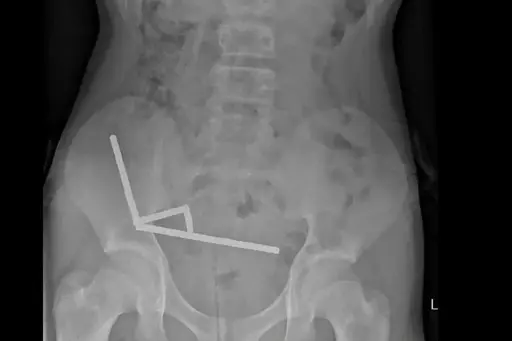

An X-ray showed the magnets had clumped together in four straight lines inside the child’s intestines.

“These appeared to be in separate parts of bowel adhered together due to magnetic forces,” they said.